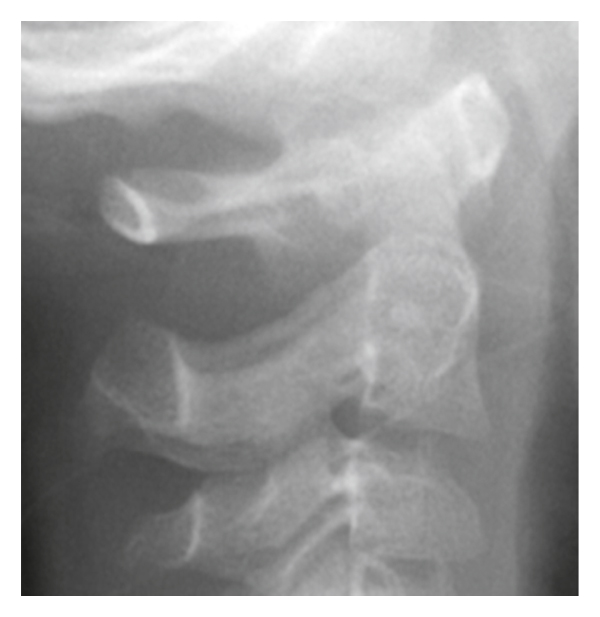

A 6-year-old boy visited our department with torticollis and neck pain that occurred after a small fight with his brother 8 days earlier. The patient had a previous history of a chronic sinus problem with a nasal discharge. The white blood cell (WBC) count was 12,800, and the C-reactive protein (CRP) level was 0.5. His physical examination showed torticollis, with head tilting, neck rotation, and a characteristic “cock-robin” position (Figure 1(a)). We diagnosed AARF (Fielding type 2) by plain radiography (Figure 1(b)) and computed tomography (CT) (Figures 1(c) and 1(d)). 3D CT showed anterior subluxation of the right C1-C2 facet (Figures 1(c) and 1(d)), and a C2 facet deformity had not appeared. His extremities appeared normal on neurological examination.

Three weeks after conservative treatment with a neck collar, AARF had not improved. We recommended inhospital care and cervical traction, but the parents denied long-term admission because they have other small children and were busy with work. Therefore, closed reduction under general anesthesia was performed and AARF improved (Figures 1(e) and 1(f)). However, AARF recurred when he woke up and walked to the bathroom 3 hours after the closed reduction.